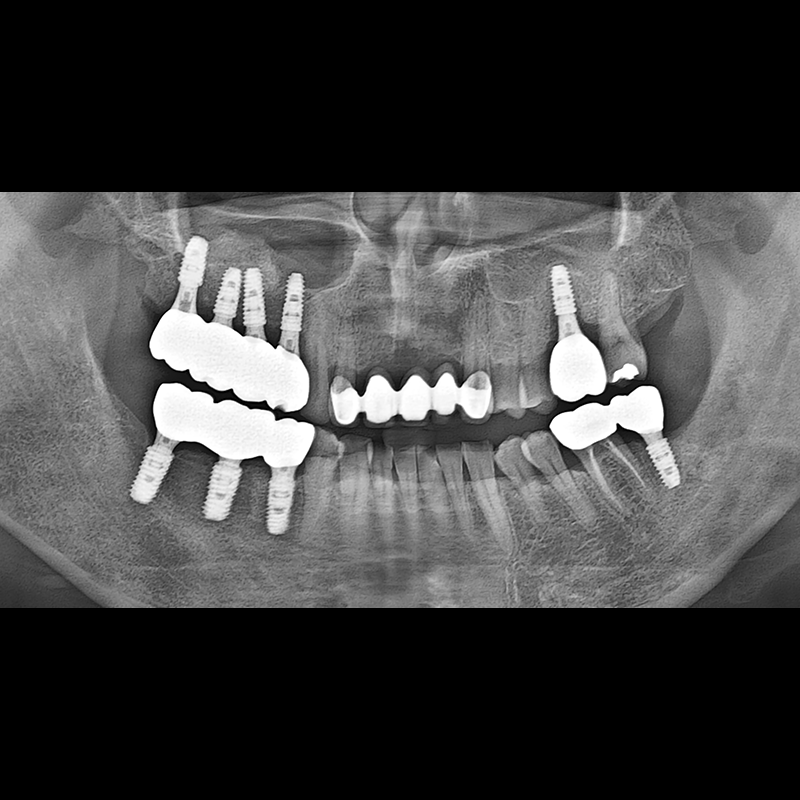

种植牙前后的照片 2025.05.30

在缺失的牙齿部分和难以挽救的牙齿位置植入了种植牙。